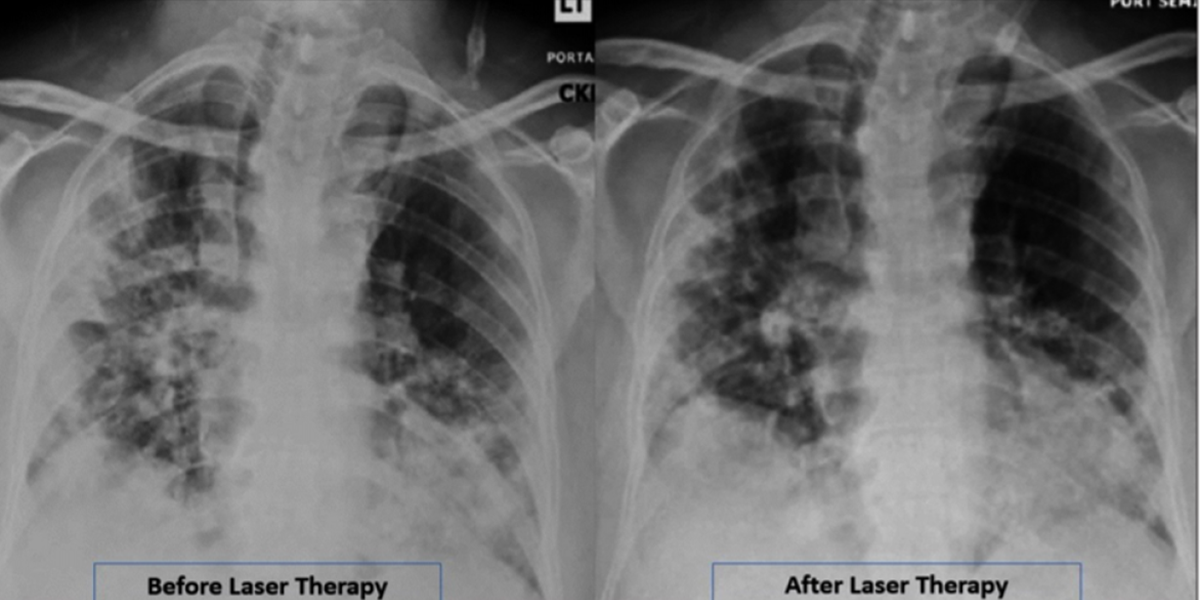

CASE REPORT A 57-year-old African American man with severe COVID-19 received 4 once-daily PBMT sessions by a laser scanner with pulsed 808 nm and super-pulsed 905 nm modes for 28 min. The patient was evaluated before and after treatment via radiological assessment of lung edema (RALE) by CXR, pulmonary severity indices, blood tests, oxygen requirements, and patient questionnaires. Oxygen saturation (SpO₂) increased from 93–94% to 97–100%, while the oxygen requirement decreased from 2–4 L/min to 1 L/min. The RALE score improved from 8 to 5. The Pneumonia Severity Index improved from Class V (142) to Class II (67). Additional pulmonary indices (Brescia-COVID and SMART-COP) both decreased from 4 to 0. CRP normalized from 15.1 to 1.23. The patient reported substantial improvement in the Community-Acquired Pneumonia assessment tool.